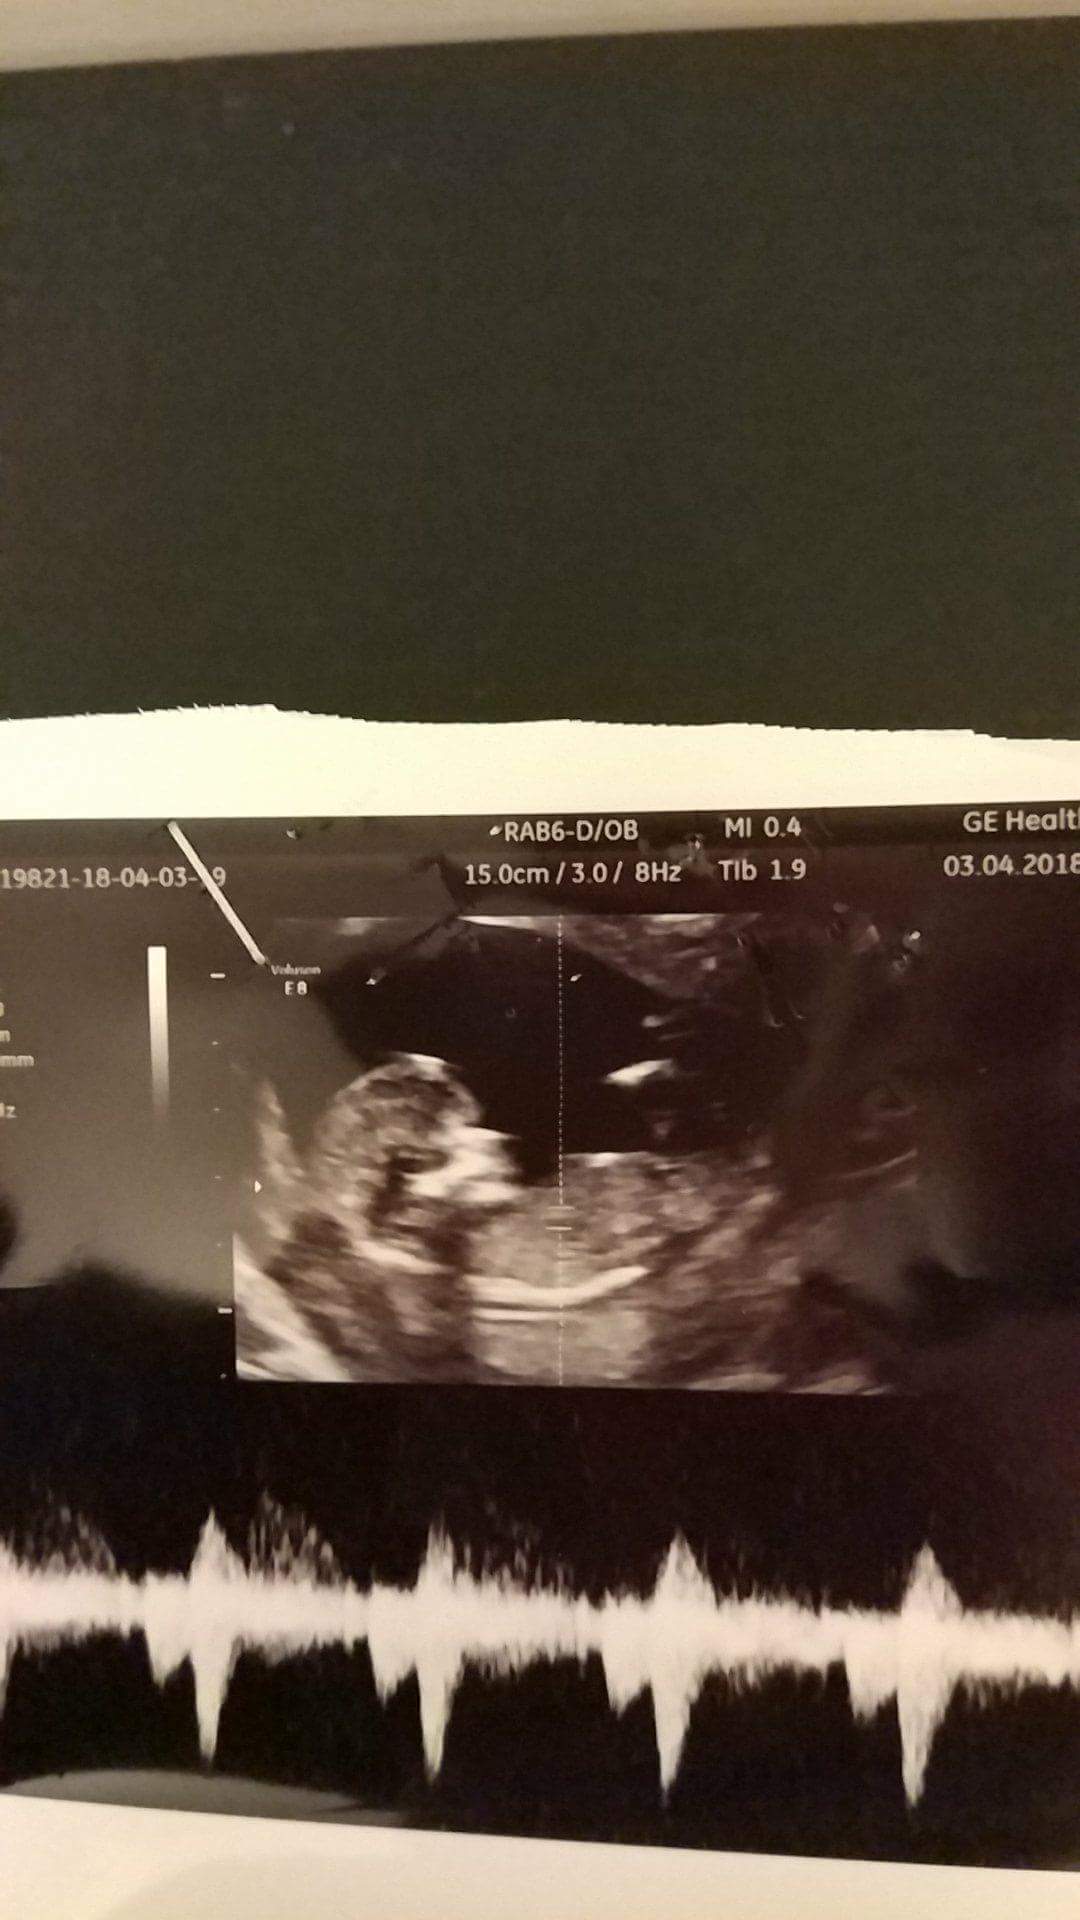

Ja już po wizycie . Maluszek pięknie rośnie , ma już 6,5 cm , ssie kciuka i podskakuje non stop Co za cudowne uczucie było go zobaczyć. Zobacz załącznik 844570